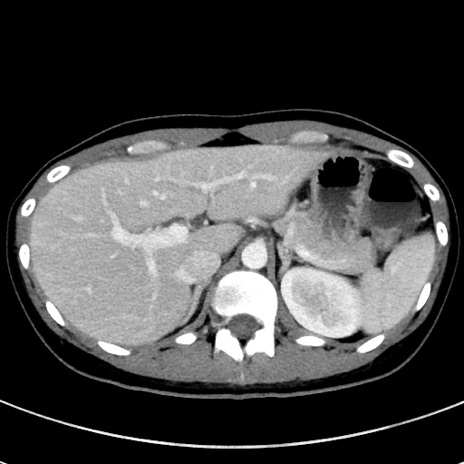

症例17(横断像)

【症例】20歳代女性

【主訴】嘔吐、下腹部痛

【現病歴】昨日夕食後に嘔吐し下腹部痛が出現。本日になっても嘔吐持続し改善しないため来院。

【身体所見】意識清明、BT 37.2℃、BP 108/67mmHg、腹部:平坦、やや硬、下腹部正中から右にかけて圧痛あり、反跳痛軽度あり、tapping pain(+)。

【データ】WBC 13600、CRP 14.94